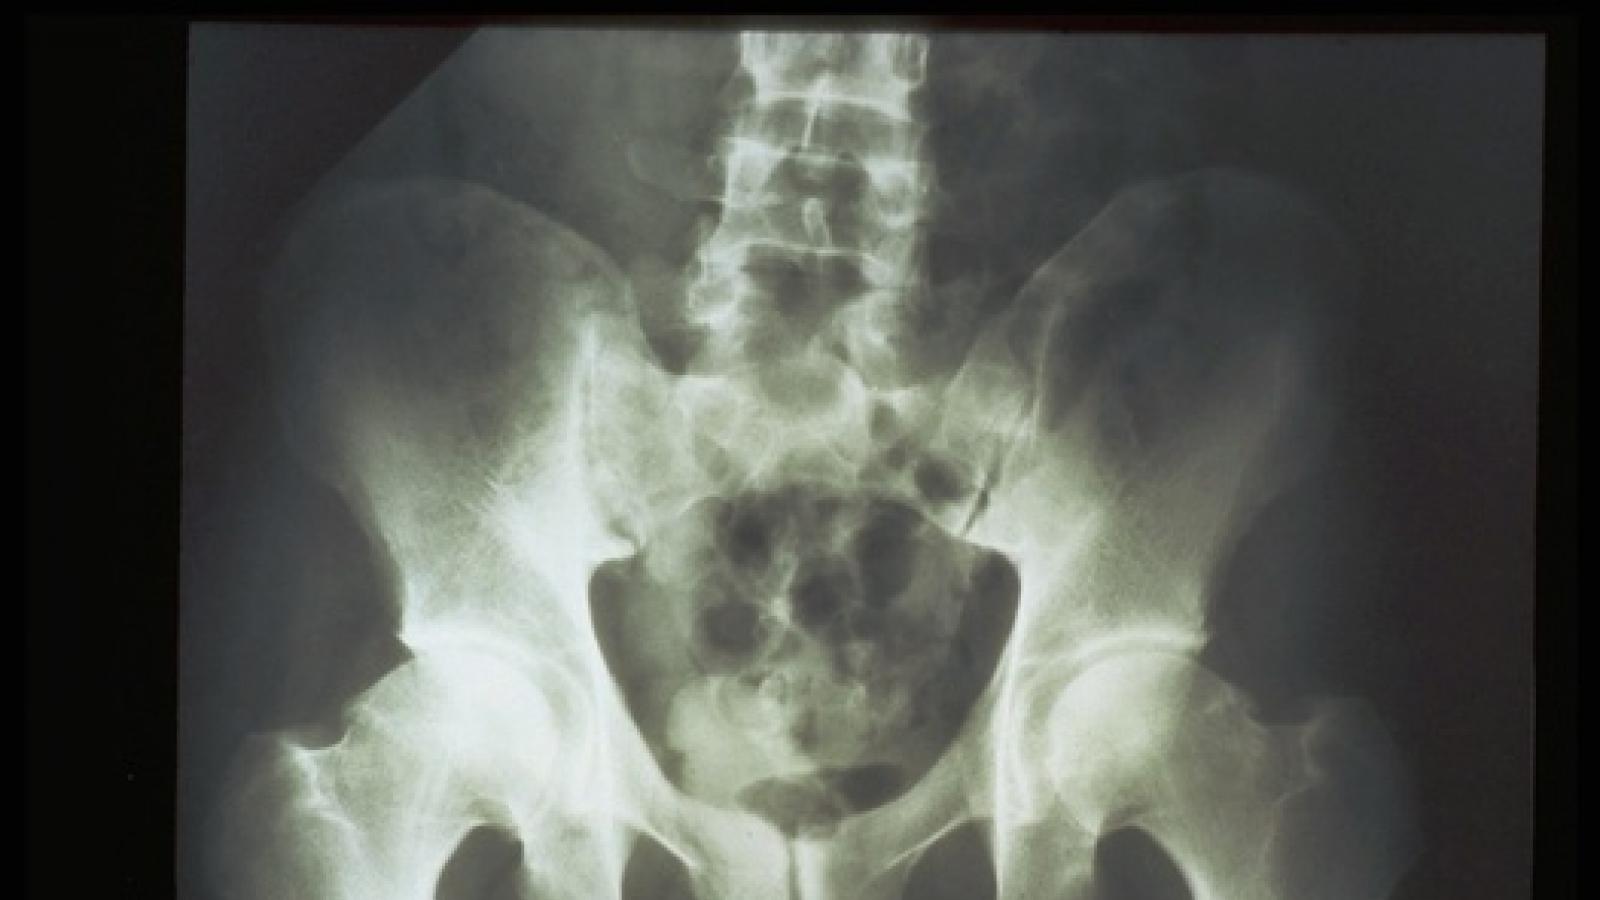

AS/Spondyloarthritis

The diagnosis of axial spondyloarthritis (axSpA) is clinical, however, there are still unmet needs, particularly in the diagnosis of early disease and evaluation of disease activity and progression. As imaging technology continues to evolve, its role in axSpA management is expected to expand, offering more precise, individualized care. Here are two studies presented at EULAR 2025.